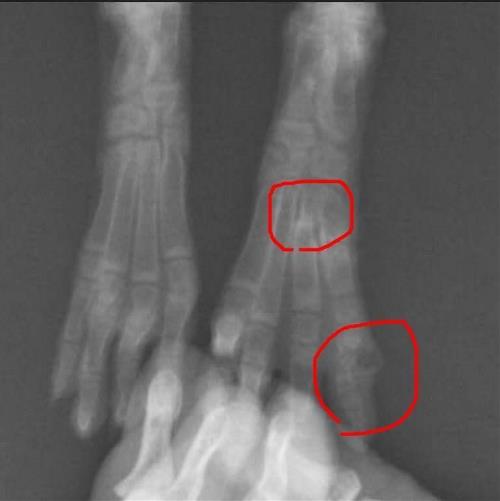

在合作金庫後面救到的小公兔,多處骨折,取名:「合庫」 希望你帶財,為自己多招些醫藥費和生活費,未來的認養人也會財源滾滾 真的非常感謝通報人與熱心兔友短期安置照顧,幫忙照顧到兔兔脫離危險期,期間密集的回報兔兔近況,穩定後再交由協會接手 2018/5/24救援,2018/6/23通報人親送協會安置,還附上一本兔兔的日記,真的非常用心 觀察後雙手明顯,跟通報人討論後,得知該兔剛救援時手還好,但最近前手打開疑似開張肢 故2018/6/24協會安排健檢+拍X光 恥骨斷裂,關節部分也有斷裂 前二隻手會向外需要再觀察,先改善環境做止滑及限制空間,之後才能確定是不是開張肢,等過陣子營養補充後再看狀況 評估後,2018/6/26兔兔由中途帶回家一對一照顧,暫不適合住在二館療養區

健康重點整理: 觀察是否開張肢 恥骨、關節斷裂 左腳趾變形有膿包 左後第3.4趾骨折 腸胃脹氣、球蟲、皮膚毛囊發炎 通報人安置影片(2018年5月底拍攝) https://www.facebook.com/rabbitsos/videos/10160761691375624/ 以下是通報人詳述救援經過: 2018/5/24傍晚6點,我在頭份市區康世美藥妝旁巷子(義民街)路過 一長滿雜草的花台,發現一小白影,是隻小幼兔在草叢裡跳& 吃雜草,對於經過的路人不會害怕躲起來。 剛好隔壁是里長家但無人在,於是我先詢問銀行保全(兔被丟棄處是 屬銀行)而得知他早上就看見兔子被丟棄在那裏。 保全說這附近沒有人養兔。因已入夜,兔會有生命危險, 經保全及銀行人員陳先生同意下先讓我救回家。 我先放置在新紙箱裡、給水及洗淨的高麗菜葉, 稍晚到處向鄰居尋借籠子都無,接後去買飼料但小兔不吃, 給高麗菜。兔寶精神不錯,體重很輕,身長約我手掌多一點。 左後腳趾上有脫毛露出紅紅外傷,目測偏外開。半夜借到一貓用外出 籠給兔子暫住。(隔兩天將其與紙箱併成一長型空間給兔) 5/25凌晨透過朋友邱先生在FB地方社團發文協尋並問有無兔友 可借籠子。中午尋得一盧小姐願助,聯繫後會帶些兔用品和糧草。 由於我無飼養任何動物經驗,上網查詢本地、 苗栗並無兔子專門醫院, 下午我出門正打算先帶兔去貓狗動物醫院看看,剛好與兔友聯繫上, 便向其討論兔仔的傷,詢求有養兔經驗的她能否協助找兔醫。 最快周日晚接兔,預計週一帶小兔去就醫。 給小幼兔取名[小草],持續吃草提摩西草、菜、水, 但兔友提供的幾種飼料也是不吃。精神好, 會好奇走跳探索與站立看我們。很親人。喜歡摸摸 觀察兔受傷的腳行動是還OK 的,應無癱瘓,但左腳有些往外開。 5/26兔小草今天有吃有喝有嗯嗯,而且終於肯吃飼料,太好了! 傍晚去兔發現地點找里長(兔遺棄處剛好隔壁是里長家, 當天里長不在),里長說附近並無人養兔,應是被棄養的, 也或許有可能與前一天本地最大廟會活動夜市裡的鼠兔攤有關?或飼 主丟棄? 兔小草依然精神、好奇張望。下午午睡前還中槍倒兩次,睡很熟。 5/27今天下午和兔友盧小姐約定帶兔小草( 明天去新竹給她熟識醫生看病及檢查), 兔友整理出一大空間給兔兔住,適應好,跳了兔子舞。 2018/6/23送來協會後給的備忘錄: 1.便盆加草盆架、水瓶都是?兔新買的, 除了這隻小兔沒有別的動物使用過,全部一併捐給協會運用。 2.今天看到協會給小兔的空間很大,而有件事: 小兔不知是癖好還是骨頭因素,他會右歪靠一個角落尿尿,比如: 他關籠一定會尿在便盆 但偏向他屁股右邊尿,故有時會從便盆邊滲漏一點尿出來。 開籠放風他就不回籠子裡的便盆尿,則會在空間裡亂尿, 但一定尿在邊線或三角角落處(非要找有個牆可以靠著尿) 協會再觀察看是他怪癖、還是跟屁股骨頭歪有關( 醫生曾說他左後肢靠屁股的骨頭有一點長歪)